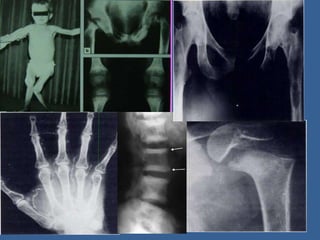

X-rays: In rickets,

• Delayed appearance of

epiphyses.

• Thickening & widening

of growth plate.

• Cupping and splaying of

metaphysis.

• Rarefaction & bowing of

diaphysis.

• Bone deformities – Genu

varum, genu vulgum,

coxavera.

X-rays: In osteomalacia,

• Milkman's pseudo

fracture(loosers zone).

• Biconcave vertebrae (from

disc pressure).

• Lateral indentation of

acetabular (trefoil pelvis or

champagne glass pelvis).

• Spontaneous fracture of

ribs, pubic ramii, femoral

neck etc.